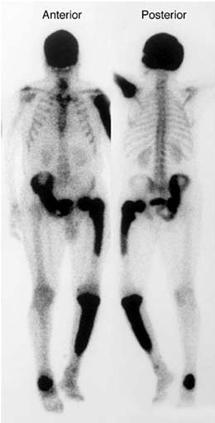

وأكد أن هذا المرض يصيب العظام ويجعله يتضخم ويزيد من سماكته مبينا أن أكثر العظام التي تتأثر من هذا المرض هي عظام الحوض والفخذ والساق واحيانا الجمجمة.

وأشار إلى أن المرض يجعل العظم ضعيف وبين أن 70% من المرضى لا يشعرون بأي أعراض لهذا المرض مبينا أن الأعراض التي قد يشعر بها الـ 30 % من مصابين هذا المرض يشعر أن هناك جهة من الجسم يكون فيها العظم أكبر من الجهة الاخرى مبينا أن ذلك يظهر في التحاليل والأشعة التي يجريها المرضى .

وبين أن أهم أعراض هذا المرض لبعض الحالات هي ألم شديد في المناطق المصابة تزداد حدته في الليل اضافة الى أم في المفاصل والمناطق القريبة منها وتشوهات في العظام وتضخمها مبينا أن ذلك يضغط على الأعصاب.